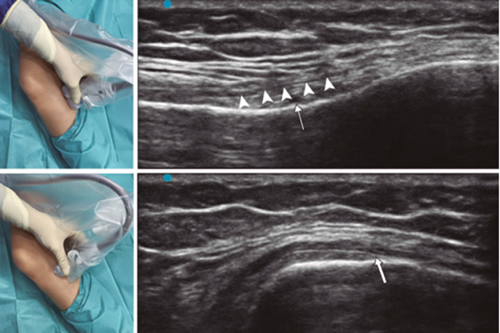

Ultrasound-guided genicular nerve radiofrequency

Fig. 3. Sonoanatomy and technique for performing superior medial genicular nerve block (SMGN). The transducer is located on the distal long axis of the femur and once the position of the SMGN (asterisks) is known, the probe is rotated 90 degrees to obtain a view of the femur short-axis (don't forget to keep the same depth that we find the SMGN on the long axis). VM (vastus medialis).

Fig. 4. Sonoanatomy and technique for performing inferior medial genicular nerve block (IMGN). The transducer is located on the proximal long axis of the tibia and we identify the vasculonervious package of the IMGN (arrow) just below medial collateral ligament (arrowheads). Then the probe is rotated 90 degrees to obtain a short-axis view of the tibia (don't forget to keep the same depth as the IMGN found on the long axis).

After performing knee asepsis/antisepsis, surgical field placement, and the sterile sheath of the high frequency linear transducer, we proceed to locate the SMGN (Figure 3). Placing the probe in a coronal plane on the inner face of the knee, we slide it cranially to visualize the junction of the metaphysis to the femoral diaphysis and the superior medial genicular artery/nerve (ASMGN), usually located near the periostium of the femur (if this neurovascular structure is not found, the junction between metaphysis and femoral diaphysis is taken as a reference). The mid-point of the transducer corresponding to ASMGN is then marked on the skin and the transducer is rotated to be placed in the transverse or axial plane to view ASMGN on the short axis (if this structure is not visible, confirm that we are at 50 % depth of the femur). In this cross-section the needle of the TRF is advanced in plane from anterior to posterior toward the ASMGN or to a depth of 50 % of the thickness of the femur. Finally, the transducer is rotated 90° again, leaving it in a coronal plane to check that the needle tip is near the ASMGN or the junction of the metaphysis and femoral diaphysis (14,16,19).

To locate the IMGN (Figure 4), we placed the transducer in a coronal plane on the inner face of the knee, sliding it caudally to identify the diaphysis junction with the tibial metaphysis and the inferomedial genicular artery/nerve (AIMGN). And we repeat the same steps we used for SMGN. If the AIMGN is not found, the reference to be taken shall be the depth of 50 % of the thickness of the tibia (14,16,19).

To locate the SLGN, the patient must be supine with the lower limb in internal rotation, obtaining good exposure to the lateral side of the thigh. We place the linear transducer in a coronal plane on the lateral side of the knee, slide it in a cranial direction to visualize the junction of the metaphysis with the femoral diaphysis and the superior lateral genicular artery/nerve (ASLGN), and repeat the same steps that we use for SMGN (14,16,19).